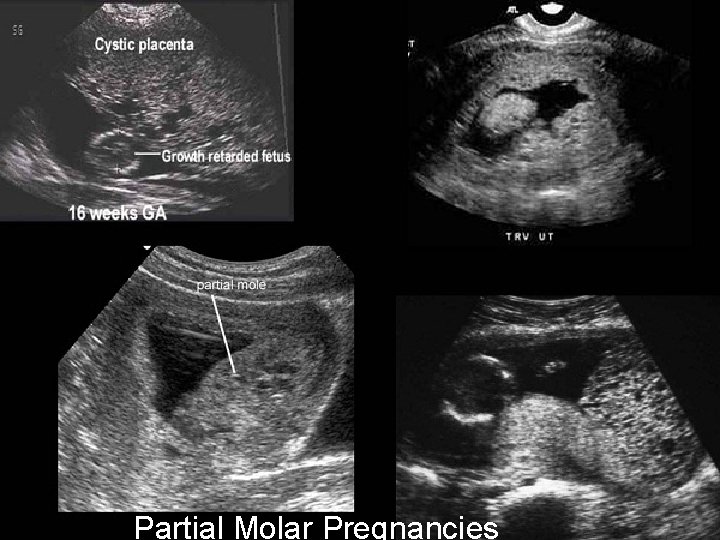

How Is Partial H. Mole Diagnosed? Classically: A thickened, hydropic placenta with fetal or embryonic tissue Multiple soft markers, including: Ø Cystic spaces in the placenta and Ø Transverse to AP dimension a ratio of the gestation sac of > 1. 5, is required for the reliable diagnosis of a partial molar pregnancy RCOG Guideline No. 38 ; 2010

Partial Molar Pregnancies